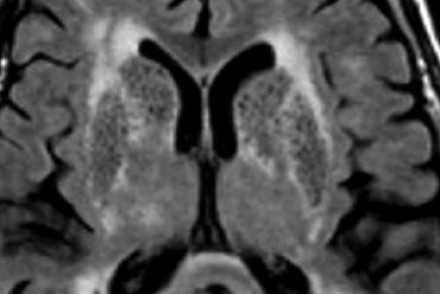

ПЕРИВАСКУЛЯРНЫЕ ПРОСТРАНСТВА ВИРХОВА-РОБИНА

Слева на Т2-взвешенной томограмме видны множественные очаги высокой интенсивности в области базальных ганглиев. Справа в режиме FLAIR сигнал от них подавляется, и они выглядят темными. На всех остальных последовательностях они характеризуются такими же характеристиками сигнала, как ликвор (в частности, гипоинтенсивным сигналом на Т1 ВИ). Такая интенсивность сигнала в сочетании с локализацией описанного процесса являются типичными признаками пространств Вирхова-Робина (они же криблюры).

Пространства Вирхова-Робина окружают пенетрирующие лептоменингеальные сосуды, содержат ликвор. Их типичной локализацией считается область базальных ганглиев, характерно также расположение вблизи передней комиссуры и в центре мозгового ствола. На МРТ сигнал от пространств Вирхова-Робина на всех последовательностях аналогичен сигналу от ликвора. В режиме FLAIR и на томограммах, взвешенных по протонной плотности, они дают гипоинтенсивный сигнал в отличие от очагов иного характера. Пространства Вирхова-Робина имеют небольшие размеры, за исключением передней комиссуры, где периваскулярные пространства могут быть больше.

На МР-томограмме можно обнаружить как расширенные периваскулярные пространства Вирхова-Робина, так и диффузные гиперинтенсивные участки в белом веществе. Данная МР-томограмма превосходно иллюстрирует различия между пространствами Вирхова-Робина и поражениями белого вещества. В данном случае изменения выражены в значительной степени; для их описания иногда используется термин «ситовидное состояние» (etat crible).

Пространства Вирхова-Робина увеличиваются с возрастом, а также при гипертонической болезни в результате атрофического процесса в окружающей ткани мозга.